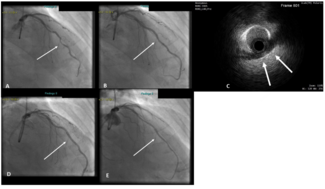

A 60-year-old male with chronic obstructive pulmonary disease and active smoking was admitted for positive treadmill test. He reported exertional chest pain 4 months ago; however, since then he had been symptom free. Echocardiography showed...